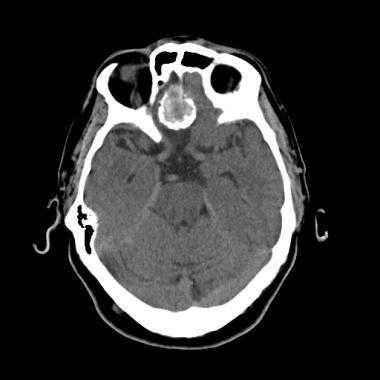

2. КТ признаки атипичной и злокачественной менингиомы:

• Бесконтрастная КТ:

о Триада ММ при КТ: внечерепное объемное образование, остеолизис, внутричерепная опухоль

о Гиперденсное образование; кальцификация минимальна или отсутствует:

- Кальцификация= обычно более низкий темп роста

о Выраженный перифокальный отек, деструкция кости

• КТ с контрастированием:

о Накопление контраста опухолевым объемным образованием

о Заметный опухолевой паннус, простирающийся на большом протяжении от объемного образования = грибовидная форма